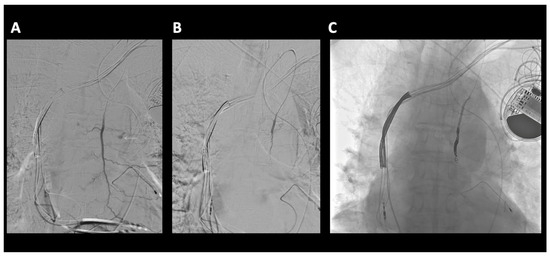

A 79-year-old male was admitted to the hospital with chest pain following a GLF. In the emergency department (ED), clinical evaluation and CT imaging revealed a sternal fracture, retrosternal hemorrhage, right pleural effusion, and left parasternal contrast extravasation. Interventional radiology was consulted, and percutaneous intervention demonstrated that a pseudoaneurysm, measuring approximately 16 mm in size, was located caudad to the clavicular head arising from a left internal mammary artery side branch (Figure 3). The patient underwent successful coil embolization, and post-procedure angiograms confirmed the effective occlusion of the left internal mammary artery, with no further visualization of the pseudoaneurysm (Figure 4). A final left subclavian control angiogram demonstrated the absence of any collateral filling of the pseudoaneurysm. Despite the successful treatment of the aneurysm, severe hepatic encephalopathy due to chronic alcoholic liver disease severely complicated recovery. Following extensive medical care, a decision was made to transition the patient to hospice care.

Figure 4. (A) Left internal mammary artery (LIMA) microcatheter DSA angiogram. Left parasternal active extravasation/pseudoaneurysm from side branch of LIMA (green arrow). (B) Microcatheter DSA LIMA post coil embolization. Coils are deposited as a bridge covering the side branch bleeding source, sometimes referred to as sandwich technique or “jailing technique”, to eliminate antegrade as well as any retrograde or collateral flow to the bleeding side branch. No further extravasation.